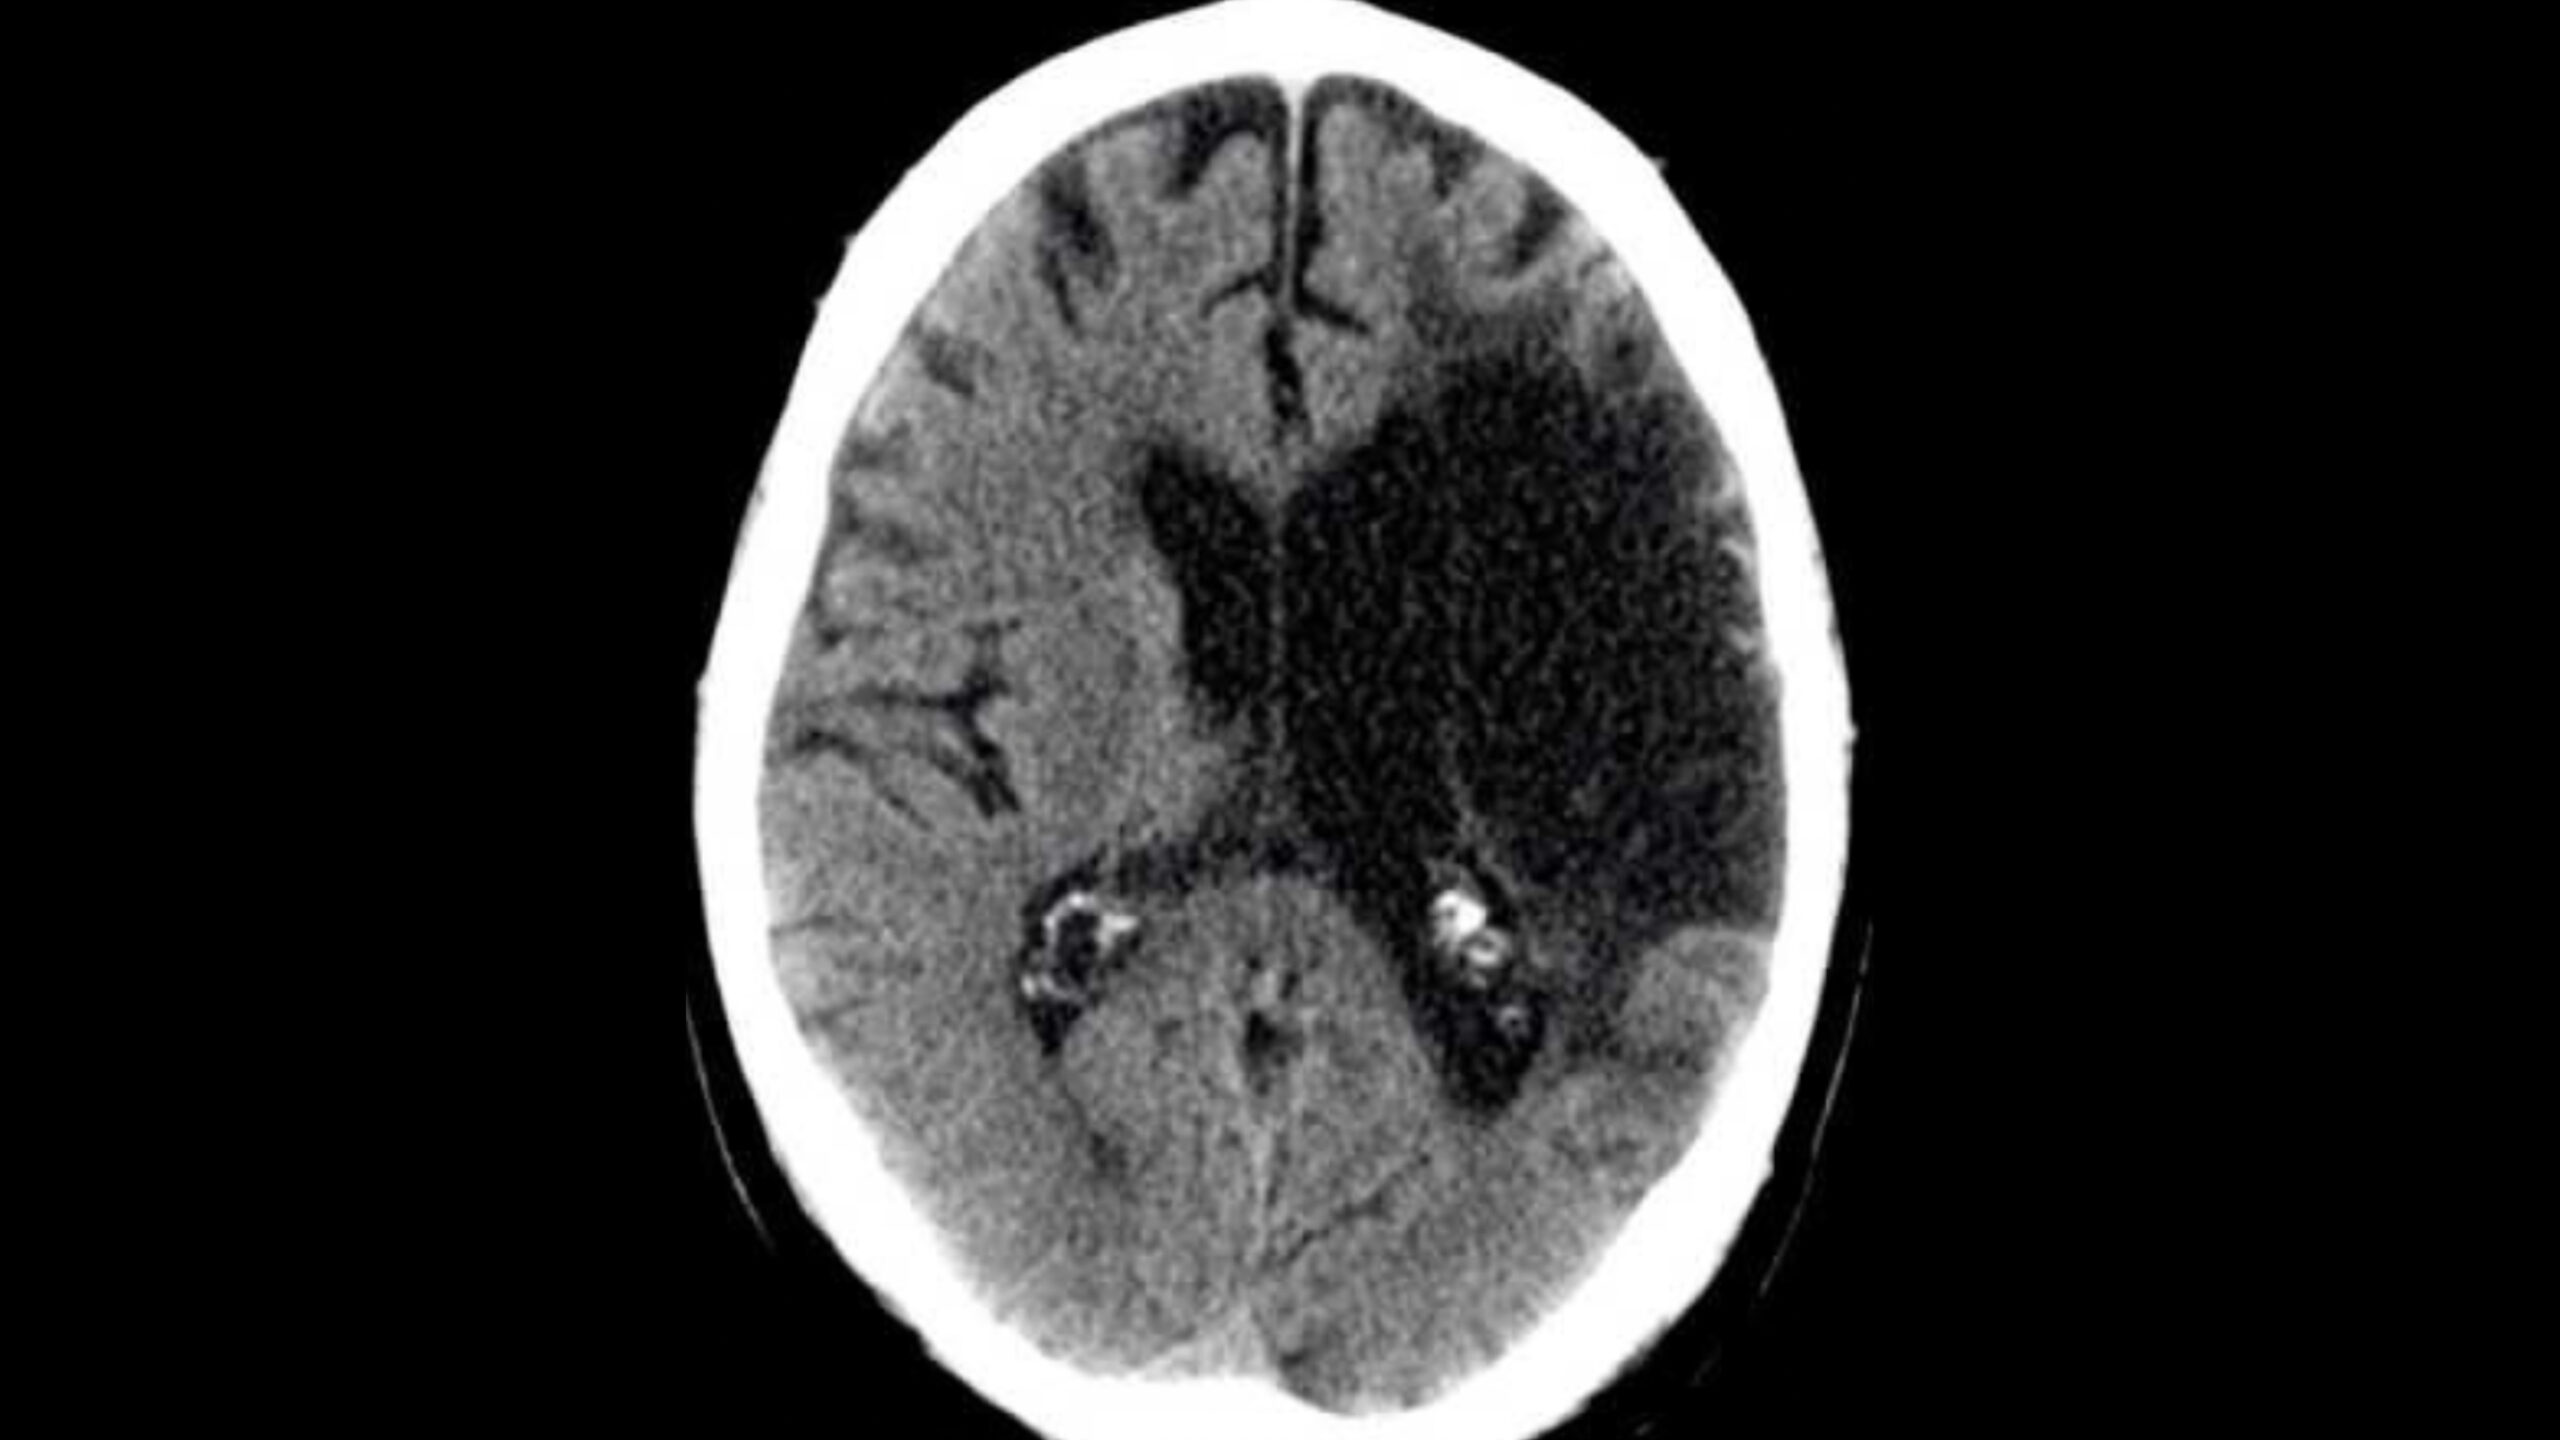

The researchers provided each AI model with the same CT brain scan showing clear intracranial pathology. Then, they asked the models to analyze the image like a radiologist—identifying the imaging technique used, the location of the pathology in the brain, primary diagnosis, key features, and potential alternative diagnoses. Overall, the findings revealed a 20 percent rate of fundamental diagnostic error across the AI models, along with concerning variabilities in interpretation and assessment.

At first, the models produced promising results, with all five correctly identifying the image as a CT brain scan. Four models also detected a key finding: an ischemic stroke near the left middle cerebral artery. However, one made a fundamental error by incorrectly misclassifying the stroke as a hemorrhage on the opposite side of the brain. In a real, clinical setting, this error could significantly impact a patient’s health, as ischemic strokes and hemorrhagic strokes require different treatments.

Even among the four AI models that reached the correct diagnosis, their explanations differed greatly. Some offered varying interpretations on when the stroke first occurred; others disagreed on alternative diagnoses and additional brain regions affected, as well as calcification. The researchers then introduced a novel surprise: They asked each AI model to grade the others’ diagnostic explanations. This cross-evaluation exposed additional inconsistencies, with some models grading more harshly than others. One model even believed the findings showed chronic brain abnormalities rather than an acute stroke and, as such, systematically penalized the others’ responses.